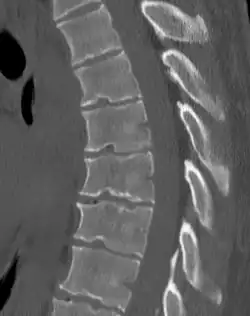

![]() | |

| Scheuermann's disease on lateral Xray of the T spine | |